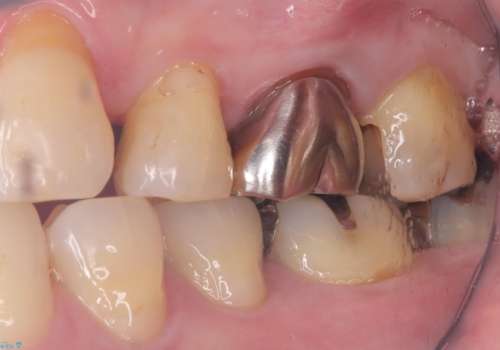

- 主訴:フロスを通したら、詰め物が取れた。適合の良いものを入れたい。

保険適用のメタルインレーが脱離しており、適合重視・咬合力が強いことからゴールドインレーでのやり替えとなりました。

フロスを通しインレーが脱離したことから、インレーと歯質との境に段差(適合不良)があった可能性があり、適合の良さや咬合力による補綴物の破折リスクを考慮し、ゴールドインレーでのやり替えとなりました。